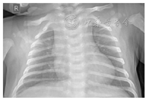

影像学检查:2月5日头颅CT、肝脾及心脏彩色多普勒超声心动图未见异常;但胸部CT提示肺门影无增大,两肺纹理增强,分布均匀,双肺野内可见散在小条状模糊影,见图1。2月10日(入院第6天)床旁胸部X线片提示左下、右上肺少许模糊影,相比入院当天CT,病灶有吸收好转,见图2。

以"新型冠状病毒肺炎""新生儿"为关键词检索截至2020年2月12日中国知网、维普网、万方等相关数据库,未见新生儿确诊COVID-19报道,本例为我国首例新生儿确诊的COVID-19患儿。本例患儿为新生儿期发病,表现为呼吸道和消化道非特异性症状,病程经过较轻,实验室及影像学检查符合COVID-19改变,与已报道儿童病例表现一致[1,2]。影像学显示入院第6天肺部病灶吸收好转,提示若没有明显的呼吸困难等进展症状和血氧饱和度的波动,则选择做床旁胸部X线片复查了解肺部病变,期望减少CT检查可能给新生儿带来的未来伤害。本例患儿父母均为确诊COVID-19患者,家庭聚集传播途径明确。患儿入院第3、4天咽拭子2019-nCoV核酸检测阳性,入院第4、5天肛拭子核酸检测阳性,结合患儿临床表现,提示存在呼吸道和消化道同时感染可能,已有此类相关传播途径报道[3,4]。需警惕在家庭护理中,如喂养等环节,用具消毒不充分及看护人员手卫生不足引起经口传播可能,但也不排除与新生儿长期卧位,呼吸道分泌物下咽有关。患儿入院后进入COVID-19隔离病房治疗,单间隔离,入温箱增加隔离屏障,专职医护人员按三级防护照护,医疗护理操作时严格手卫生和感染防护,定期开窗通风,患儿排泄物和分泌物放入感染专用垃圾袋,并用消毒剂喷洒袋内外表面后入感染专用垃圾桶。因为新生儿感染症状不典型和缺乏相关报道,容易忽视新生儿感染,通过本例新生儿病例,特别提出家庭中需重视新生儿COVID-19的看护及管理问题。针对目前2019-nCoV感染流行情况,家庭成员或密切接触者有疑似或确诊COVID-19时,需警惕新生儿感染可能。因新生儿感染后可能表现为无症状或不典型症状,对新生儿应采用保护性隔离措施,进行专人专护,避免密切接触。在喂养、清洁口腔、更换尿不湿或其他有身体接触行为时,应注意个人防护,加强手卫生,新生儿护理用具用后即进行有效消毒,减少家庭成员间传播。医疗机构应对入院2019-nCoV感染新生儿进行隔离,并减少医务人员流动性。加强病区通风、清洁消毒工作,在基础防护的同时,若进行可能发生体液、分泌物喷射或飞溅,如吸痰、气管插管等工作时,要求加强防护。病区实行封闭式管理,停止一切探视、对家长授课、母乳喂养等行为。需要强调的是,患儿咽拭子病毒核酸检测阴性后仍有肛拭子病毒核酸检测持续阳性,因此不能仅靠咽拭子病毒核酸检测阴性提前解除隔离,建议监测至肛拭子病毒核酸检测阴性。无明显症状新生儿可作为传染源,患儿产生的废弃物、分泌物及排泄物等应做好标记,严格按感染性医疗废物处理。患儿出院后对所在房间及护理单元进行终末消毒。